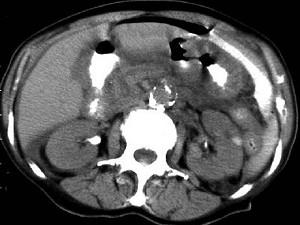

问题 男,44岁,突然中上腹痛,压痛,反跳痛,腹肌紧张,发热,白细胞计数升高,CT检查如图,最可能诊断是 ( )

选项 A、胰腺癌 B、胃癌 C、慢性胰腺炎 D、胃小弯溃疡穿孔 E、急性胰腺炎

答案 D